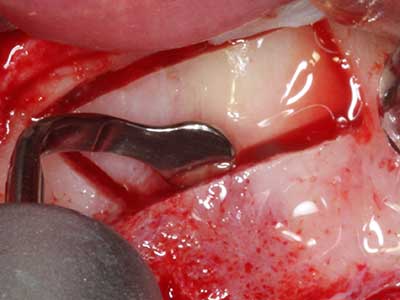

Fig. 18: preparazione di una copertura corticale con sega piezoelettrica per osso (Piezomed, W&H).

Fig. 19: sito chirurgico dopo neurolisi e rimozione dell'osteoma.

Fig. 20: la copertura ossea rimossa viene riadattata e fissata con una vite per osteosintesi (KLS Martin, Tuttlingen).